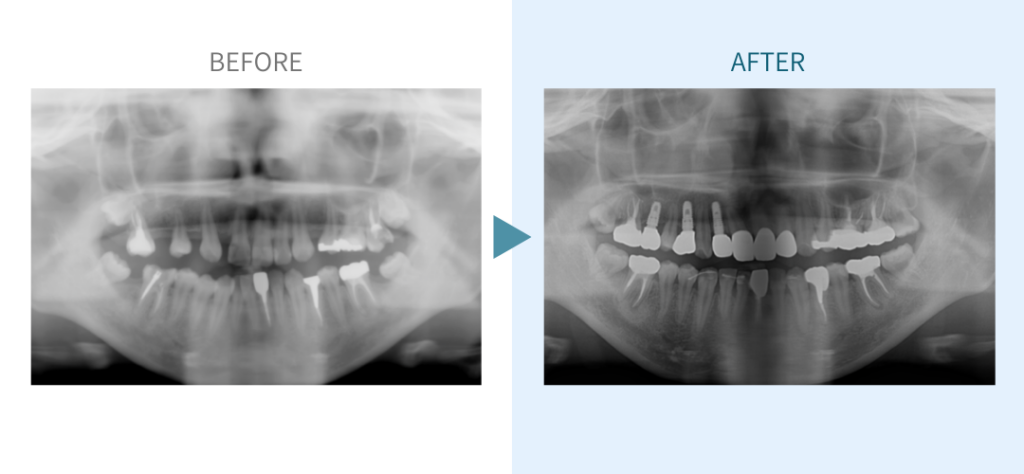

デンタルチームジャパンでは、サイナスリフト(上顎洞底挙上術)や骨造成など、他院で「骨が足りない」と断られた難症例にも対応しています。

私たちは、難症例に関する治療法を学会でも発表しており、その豊富な実績と技術力が評価され、全国から患者様が来院いただいております。

こちらではその一部の症例についてご紹介します。